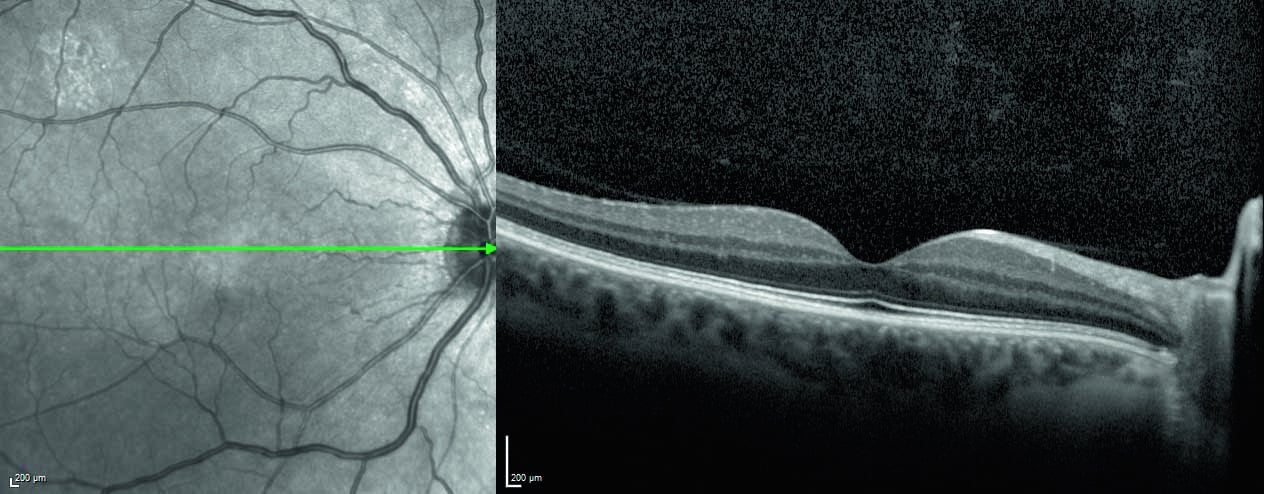

The SPECTRALIS SHIFT technology enables adaptation to the unique needs of the patient and clinic workflow by offering changeable OCT scan speeds. Use 20 kHz for maximum detail in eyes that are challenging to image, 85 kHz for optimal balance of speed and image quality, and 125 kHz for rapid scanning in time-sensitive or high-volume settings.